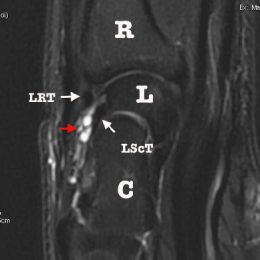

C - IRM, Coupe sagittale T2 : le kyste longe la face superficielle du ligament radio-scapho-triquetral dorsal .

Kyste synovial de la face dorsale du carpe.